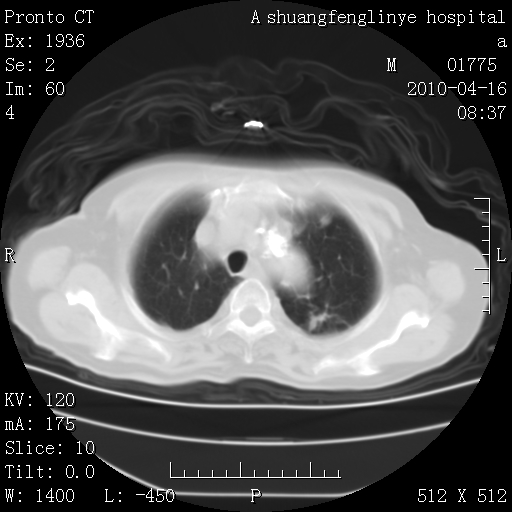

标题: CT25784:咳痰、请会诊!结核? [打印本页]

标题: CT25784:咳痰、请会诊!结核?

考虑左肺上叶增殖灶、纤维灶。

支持结核

慢支肺气肿,左上陈旧性结核,主动脉冠脉钙化

1)左肺上叶结核(纤维、增殖病灶)。2)冠状动脉及主动脉钙化。

1)左肺上叶结核(纤维、增殖病灶)。2)冠状动脉及主动脉钙化。肺动脉高压